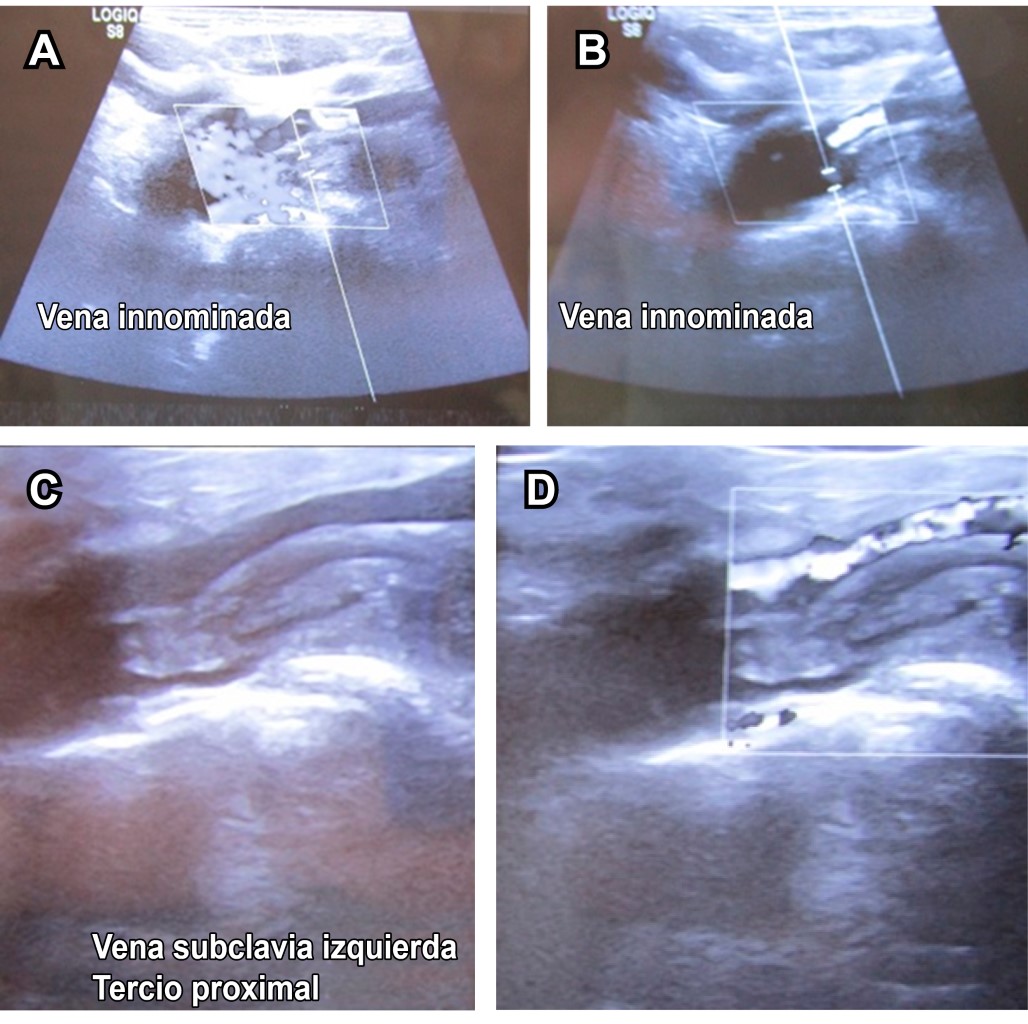

Masculino de 20 años de edad, estudiante, practicante de fisiculturismo seis días/semana. Acude a consulta de rehabilitación por presentar dolor con intensidad 5/10 en escala visual analógica (EVA), y edema de extremidad torácica izquierda de 24 horas de evolución. Como antecedente menciona haber incrementado en los dos días previos carga importante en ejercicios de extremidades superiores. A la exploración dirigida, venas ingurgitadas en miembro torácico izquierdo, con edema suave sin signo de Godet con arcos de movilidad completos de hombro, codo, carpo y manos, fuerza muscular 5/5 en escala de Daniels para todos los músculos de extremidades superiores, reflejos osteotendinosos normales, pulsos y llenado capilar normal; como dato de interés, dolor moderado en brazo al efectuar elevación de miembro torácico izquierdo por arriba de la cabeza. Por las características atléticas del paciente, el esfuerzo realizado y la evolución aguda se efectúa diagnóstico presuntivo de trombosis de vena subclavia izquierda (síndrome de Paget-Schroetter). Se solicita ultrasonido, el cual lo confirma (Figuras 1, 2 y 3). El paciente se derivó como urgencia a angiología y cirugía vascular.

La trombosis venosa profunda (TVP) primaria de miembros superiores a nivel de las venas axilar-subclavia es una enfermedad rara, se le denomina síndrome de Paget-Schroetter,1,2 también conocida como trombosis de esfuerzo, ya que por lo general se presenta de manera repentina tras el desarrollo de una actividad vigorosa con la extremidad superior3 (como en el caso expuesto), representa aproximadamente de 1 a 4% de todos los casos de TVP. Su incidencia anual se estima de uno a dos/100,000 y ante sospecha diagnóstica, el estudio inicial de elección es el ultrasonido Doppler.4

Figura 1

Figura 2

Figura 3